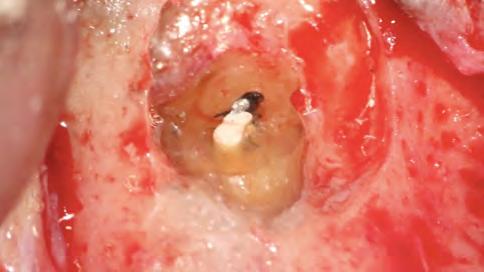

Después del retratamiento endodóntico convencional, el paciente fue sometido a una microcirugía apical. La osteotomía y la apicectomía se realizaron con el uso de una punta ultrasónica (W1CVDentus-Brasil). El fragmento apical del cono de plata se hizo visible en una ampliación de 12,5x (Figura 6). A fin de remover el fragmento apical, se utilizó una punta de ultrasonido P1M (Helse Ultrasonic - Brasil) (Figura 7, Figura 8). Después de la remoción microquirúrgica

del cono de plata, la preparación retrógrada fue realizada con la misma punta ultrasónica (Figura 9).

Figura 6 - Tercio apical después de apicectomía

ambientes húmedos, inducción y conducción en la formación de tejidos duros, cementogénesis con consecuente formación de adherencia periodontal normal, hacen el material más adecuado para estas situaciones clínicas. En este caso, se utilizaron nuevos materiales biocerámicos para obturación de la cavidad retrógrada. En primer lugar, el BIO-C® REPAIR (Angelus - Brasil) se utilizó para obturar el espacio en el conducto radicular. Un tapón apical de BIO-C® REPAIR (Angelus - Brasil) fue colocado sobre la raíz, sellando la retro cavidad (Figura 10, Figura 11).